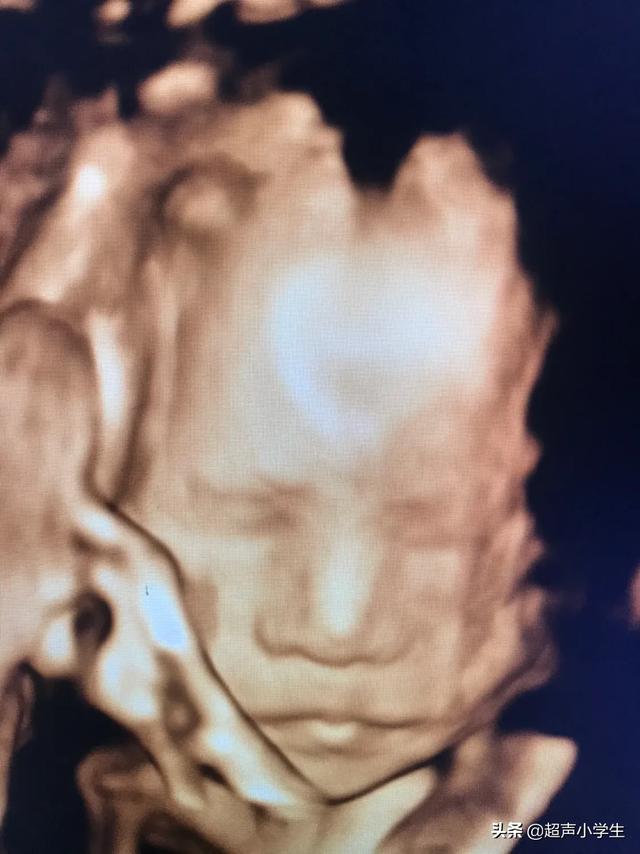

1、首先四维彩超主要检查面部畸形:四维彩超检查时重点观察胎儿双眼与眼眶是否等大、等圆,以及眼距测量,硬腭、软腭及上唇弧型曲线是否连续中断等。接下来筛查胎宝宝的颈部,看是否有异常包块。

还有四维彩超可以记录宝宝的第一次有照片的容貌,也算是宝宝人生的第一张照片,运气好的话还是带微笑的照片,这个很有纪念意义。